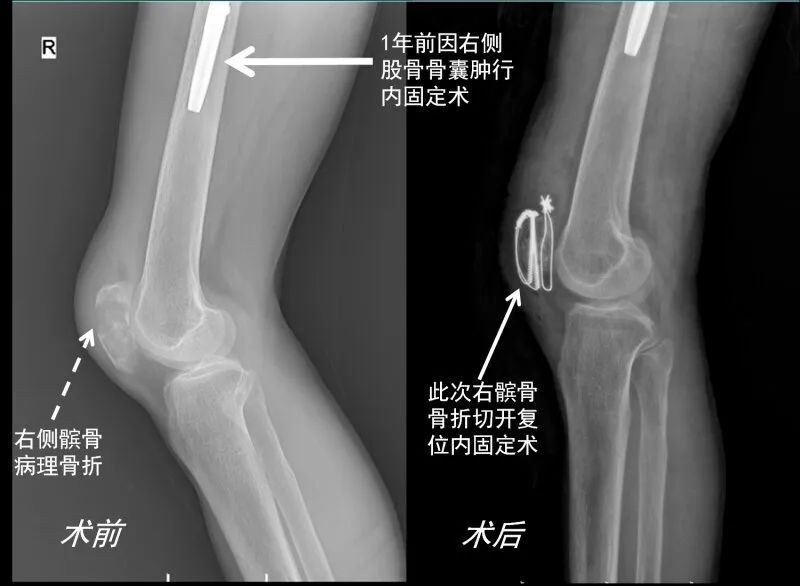

42岁的郝先生,不小心摔了一跤,虽然是臀部着地,但伤后却出现右膝肿痛和活动受限,于金山区亭林医院急诊拍片显示右侧髌骨骨折(图1),遂住院接受了右侧髌骨骨折切开复位内固定术(图2),并留取了活检标本,看似非常普通的一个病例,已经准备出院了,这个简单的故事,似乎一开始就马上要结束了。

图1 图2

根据图1可见,除了髌骨粉碎性骨折之外,还可见右侧股骨中下段透亮度明显增加、骨小梁稀疏、骨皮质也显著变薄。追问病史,患者于1年前因右大腿疼痛检查发现右股骨骨囊肿形成并接受了内固定手术治疗(图1b可见内固定钢板)。患者出院之后病理报告才出来(图3),显示骨组织很少,绝大部分被纤维组织代替,同时可见大量多核巨细胞,病理科的同事立即意识到这不是一例简单的外伤引起的骨折,而是一种病理性骨折,高度怀疑甲旁亢引起的纤维囊性骨炎或骨巨细胞瘤。